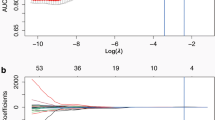

A total of 235 18F-FDG PET/CT patients with pathologically or follow-up confirmed lung adenocarcinoma (n = 131) or tuberculosis (n = 104) were retrospectively and randomly divided into a training (n = 163) and validation (n = 72) cohort. Based on the Transparent Reporting of Multivariable Prediction Model for Individual Prognosis or Diagnosis (TRIPOD), this work was belonged to TRIPOD type 2a study. The Mann-Whitney U test and least absolute shrinkage and selection operator (LASSO) algorithm were used to select the optimal predictors from 92 radiomic features that were extracted from PET/CT, and the optimal predictors were used to build the radiomic model in the training cohort. The meaningful clinical variables comprised the clinical model, and the combination of the radiomic model and clinical model was a complex model. The performances of the models were assessed by the area under the receiver operating characteristic curve (AUC) in the training and validation cohorts.

In the training cohort, 9 radiomic features were selected as optimal predictors to build the radiomic model. The AUC of the radiomic model was significantly higher than that of the clinical model in the training cohort (0.861 versus 0.686, p < 0.01), and this was similar in the validation cohort (0.889 versus 0.644, p < 0.01). The AUC of the radiomic model was slightly lower than that of the complex model in the training cohort (0.861 versus 0.884, p > 0.05) and validation cohort (0.889 versus 0.909, p > 0.05), but there was no significant difference.